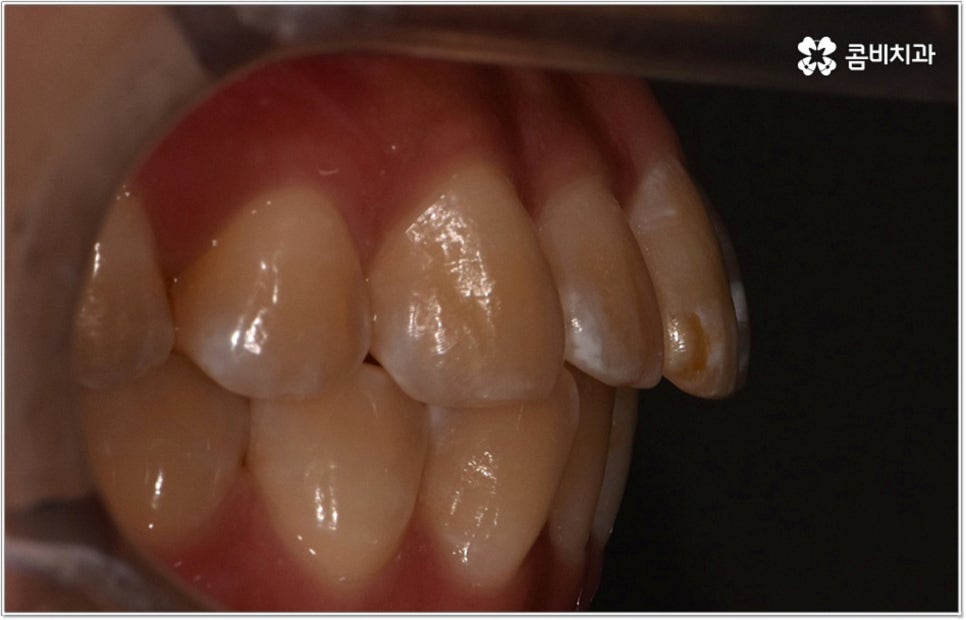

특히 위아래 치아가 제대로 맞물리지 않는 분들 중 시간이 지날수록 치열이 비정상적인 저작 과정에 적응하는 쪽으로 영향을 받아 부정교합의 정도가 심해지고 턱관절 건강까지 악화되는 일이 발생할 수도 있기 때문에 주의하실 필요가 있는데요. 미리 크게 걱정을 하거나 지레 짐작으로 막연하게 두려움을 가지고 내원 자체를 미루시기 보다는 현재 자신의 상황이 어떤지부터 먼저 상세하게 체크해보고 그에 따라 필요한 치료 과정이 무엇인지도 한 번 알아두면 좋겠다는 마음으로 치과에 방문하셔서 부정교합의 종류 (주걱턱, 돌출입, 덧니, 개방교합 등) 와 정도를 꼼꼼하게 검사한 후 숙련된 의료진과 차근차근 상담을 해보시면 부정교합으로 인한 불편함을 줄이는데 도움이 되실 거예요.

만약 치아가 이동할 범위를 계산해 봤을 때 공간이 충분하다면 굳이 치아를 뽑지 않고 비발치치아교정 과정으로 치료할 수 있어요. 제일 뒤에 있는 어금니를 더 후방으로 이동시키거나 치간 삭제, 악궁확장장치 등으로 치아 사이를 벌려서 이동 공간을 확보할 수 있으면 비발치치아교정 이 가능한 거예요. 이 때 부정교합이 심각하거나 악골이 치아에 비해 많이 작은 경우, 구조적인 원인을 개선할 필요성이 있는 경우 등 발치 교정을 하는 것이 꼭 필요한 케이스라면 치아를 뽑아주어야 하며, 환자분들의 상황에 따라 다르지만 보통은 소구치를 발치하는 경우가 많이 있습니다.

대다수의 환자분들은 되도록 치아를 뽑지 않았으면 하고 바라시겠지만 발치교정이 꼭 필요한 케이스에서 비발치치아교정 을 고집하게 되면 치열을 원하는 정도까지 움직이기 어렵고 (예를 들어 만약 돌출입이라면 만족할 만한 수준까지 들어가지 않을 수도 있음) 결과적으로 상하 부정 교합 역시 제대로 개선되지 않을 수 있어요. 이 때 다양한 케이스를 다뤄보고 뛰어난 노하우를 가지고 있는 의료진과 충분히 상담을 해 보시고 또한 모르페우스를 이용하여 교정 치료를 받고 난 후의 미래 예상 모습을 살펴 보고 나면 발치 과정의 필요성에 대해 스스로 이해하는데 도움이 되실 거예요.